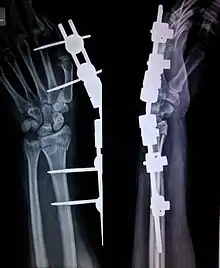

التثبيت الخارجي (بالإنجليزية: External fixation) هو أسلوب جراحي يستخدم لتثبيت كسور العظام باستخدام جهائز تدعم العظم من الخارج.[1][2][3]

يجرى هذا النوع من رد الكسور في غرفة العمليات تحت تعقيم جراحي كامل، وتحت تخدير كلي أو جزئي في الأغلب. وفيه تُثقب ثقوب في أجزاء غير مكسورة من العظمة أعلى الكسر وأسفله، ويجري إدخال مسامير أو أسلاك معينة في هذه الثقوب، ثم توصل بهذه المسامير والأسلاك قضبان أو أجزاء معدنية دائرية أو شبه دائرية ذات مفاصل لتدعيمها من الخارج. وتسوغ هذه المفاصل الخارجية تعديل وضع الكسر من الخارج دون اللجوء إلى الشق الجراحي.